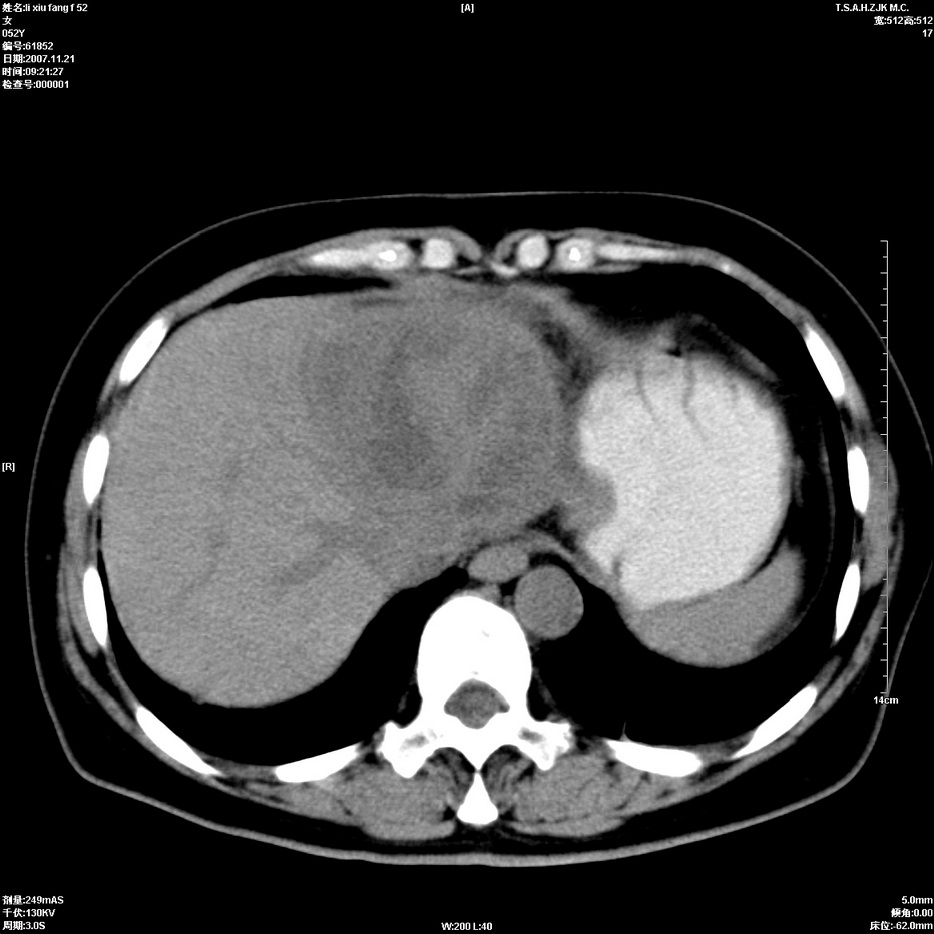

标题: CT12858:女,52岁,胎甲球蛋白861肝左叶占位,肝癌。下腔静 [打印本页]

标题: CT12858:女,52岁,胎甲球蛋白861肝左叶占位,肝癌。下腔静

肝左叶巨大低密度灶肿块,增强符合快进快出表现,有动静脉交通支;静脉期,下腔静脉内有充盈缺损,afp明显升高,支持肝癌并下腔静脉癌栓形成。

以下是引用拾荒者在2008-4-15 22:57:00的发言:[br]肝左叶巨大低密度灶肿块,增强符合快进快出表现,有动静脉交通支;静脉期,下腔静脉内有充盈缺损,afp明显升高,支持肝癌并下腔静脉癌栓形成。